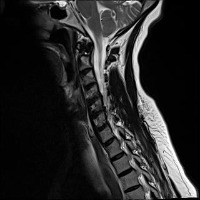

Classes (24)

Annular Disc Relaxationrotation

Annular Tearrotation

Annular disc relaxationrotation

Annular tearrotation

Degenerated discrotation

Degenerative Disc Diseaserotation

Demyelinating Plaquesrotation

Demyelinating plaquesrotation

Disc Bulgerotation

Disc Bulgerotationtrack_idkeyframe

Disc Herniationrotation

Disc Protrusionrotation

Disc Relaxationrotation

Disc bulgerotation

Disc bulgerotationtrack_idkeyframe

Disc herniationrotation

Disc protrusionrotation

Disc relaxationrotation

Fracturerotation

Hemangiomatarotation

Osteophytesrotation

annular tearrotation

diffuse disc bulge with neural compromiserotation

stenosisrotation